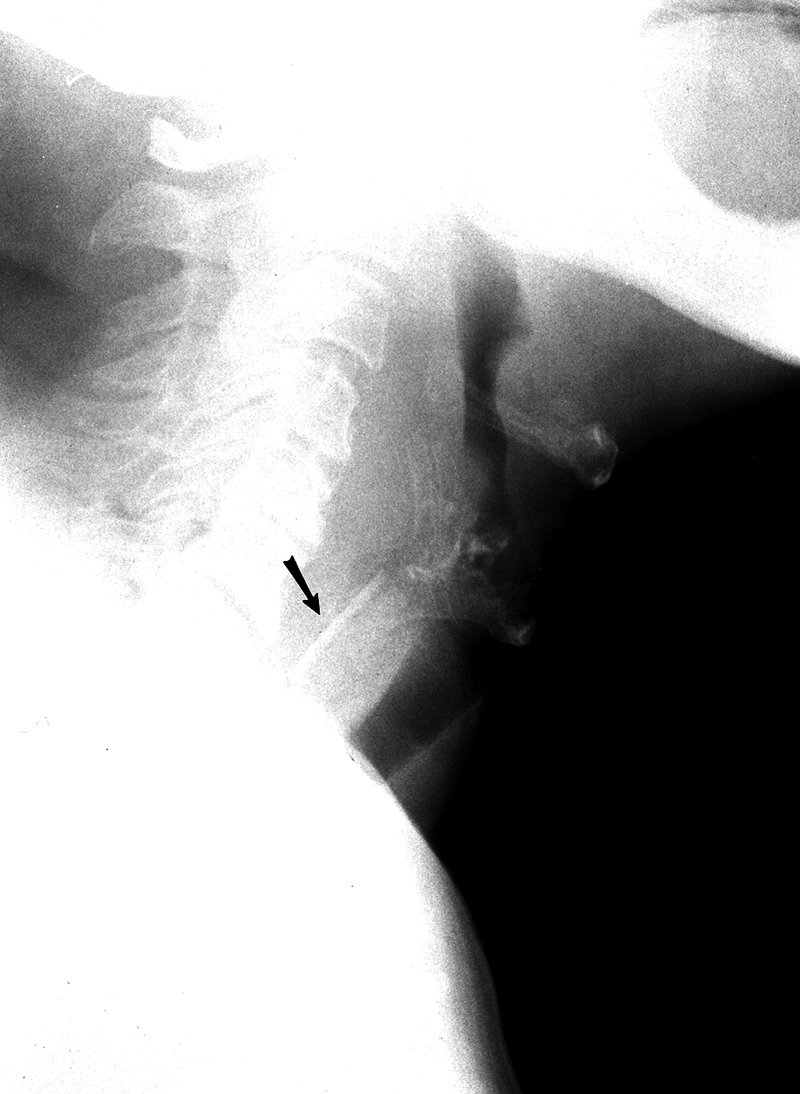

68 year-old man with difficulty swallowing after eating fish. A bone (arrow) had perforated the hypopharyngeal wall and was lodged in the soft tissues of the neck. Indirect laryngoscopy was negative, and the bone was removed at surgery after an unsuccessful endoscopy. From Hunter, 1994 |